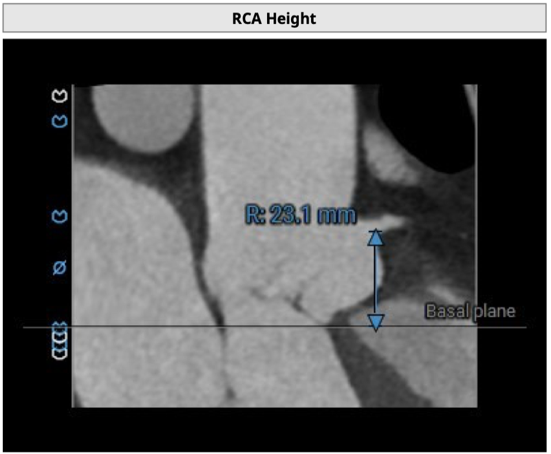

右冠开口高度23.1mm